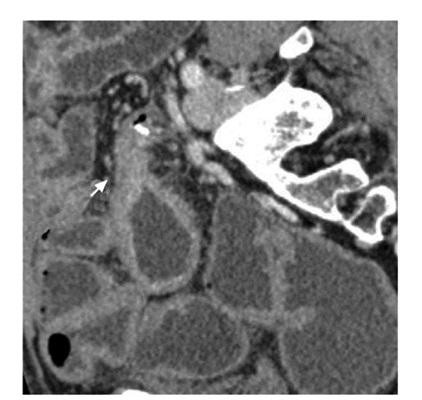

• 摘要: 肠腔狭窄是常见的克罗恩病(Crohn's disease,CD)并发症,15%的CD患者在首诊10年内可发展为肠腔狭窄。CD并发肠腔狭窄根据病理类型可分为炎症型、纤维型及混合型,炎症型为主的患者可通过药物治疗缓解症状,而纤维型为主的患者则只能通过介入或手术治疗,故采用影像学手段全面评估狭窄肠段的数目、部位、形态,并区分肠壁炎症和纤维化程度,对于临床决策十分重要。近年来,多项影像学新技术在鉴别狭窄肠壁炎症及纤维化方面取得了较大进展,有望在临床推广应用,进一步提高CD并发肠腔狭窄的诊疗。本文综述主要影像学手段包括内镜、CT、MRI、经腹超声等对肠腔狭窄的诊断价值,以期为临床提供参考。

Abstract: Intestinal stricture is one of the most common complications of Crohn's disease(CD). About 15% of CD patients can develop intestinal stricture within the first 10 years after diagnosis. CD complicated with intestinal stricture can be divided into inflammatory, fibrous and mixed types according to pathological changes. Patients with the inflammatory type can alleviate symptoms by drug treatment. In patients with the fibrous type, the affected intestinal segments can only be treated by interventional or surgical treatment. Therefore, it is very important for clinical decision-making to comprehensively evaluate the number, location and shape of narrow intestinal segments, and to distinguish the degree of inflammation and fibrosis of the intestinal wall. This article reviews the sensitivity and specificity of the main imaging methods including endoscopy, CT, MRI, and trans-abdominal ultrasound in the diagnosis of intestinal stricture. In recent years, many new imaging techniques have made great progress in differentiating inflammation and fibrosis of the narrow intestinal wall, which is expected to be widely used in clinical practice and to further improve the diagnosis and treatment of CD complicated with intestinal stricture.